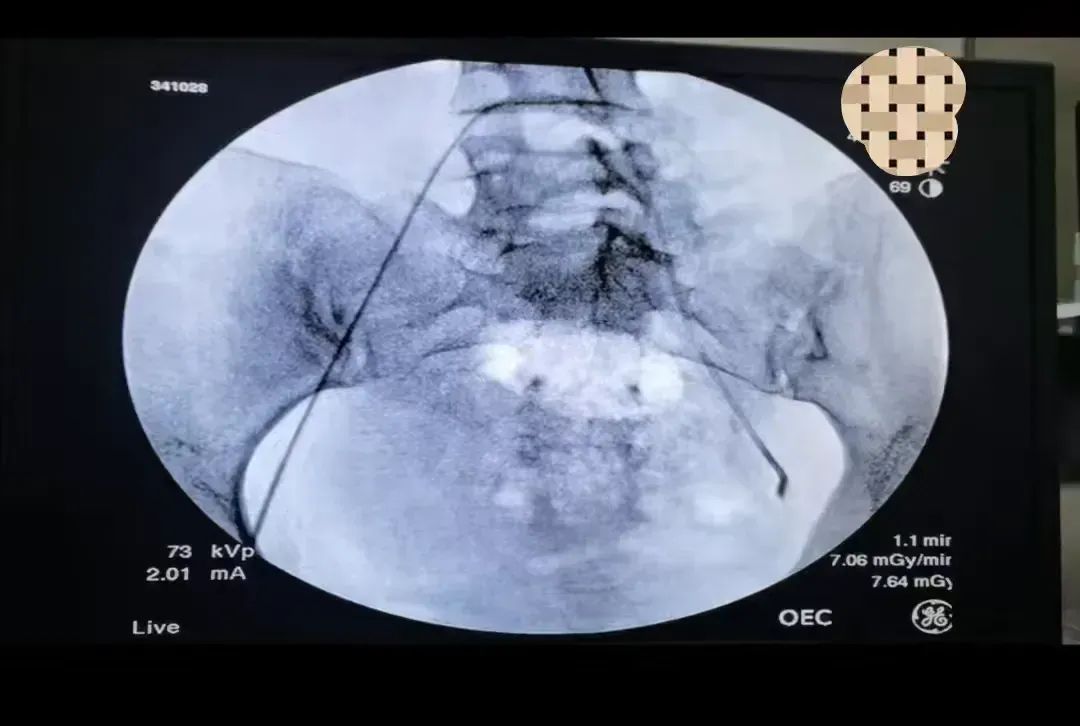

38岁的段女士因子宫腺肌瘤伴中度贫血面临手术治疗甚至切除子宫的困境。区中医医院妇产科主任胡玉华结合病情和患者需求,为患者制定了创伤小,恢复快的子宫动脉栓塞介入治疗方案。在介入团队和麻醉团队的协同合作下,妇科团队仅30分钟便顺利将导管精准插入子宫动脉,通过注入栓塞物质,阻断了子宫肌瘤的血液和营养供应。手术后,段女士大腿根部只有一个“小针眼”,很快顺利出院。

该治疗是通过影像学检查(如超声、CT、MRI等)对患者的子宫腺肌瘤进行全面评估,确定病灶的具体位置和大小,在数字减影血管造影(DSA)设备的引导下,将导管准确送入供应病灶的动脉,并注射栓塞剂,这一操作如同截断了肌瘤的“粮草”,阻断了其血液和营养供应,使其慢慢“饿死”。治疗优势:无痛微创,快速恢复与传统手术相比,血管栓塞介入治疗无需开刀,仅需在大腿根部做一个微小的穿刺口即可完成操作。治疗过程中,患者几乎不会感到疼痛,术后也无需长时间卧床休息,通常在几天内即可恢复正常生活。许多患者在接受治疗后表示,整个过程非常轻松舒适,几乎没有不适感。除了身体上的恢复,血管栓塞介入治疗还显著提升了患者的生活质量。由于该方法可以有效缩小或消除子宫腺肌瘤,患者的症状如月经量过多、经期延长、腹痛等明显减轻,甚至完全消失。许多患者在治疗后重新找回了自信和活力,生活质量得到了极大的改善。